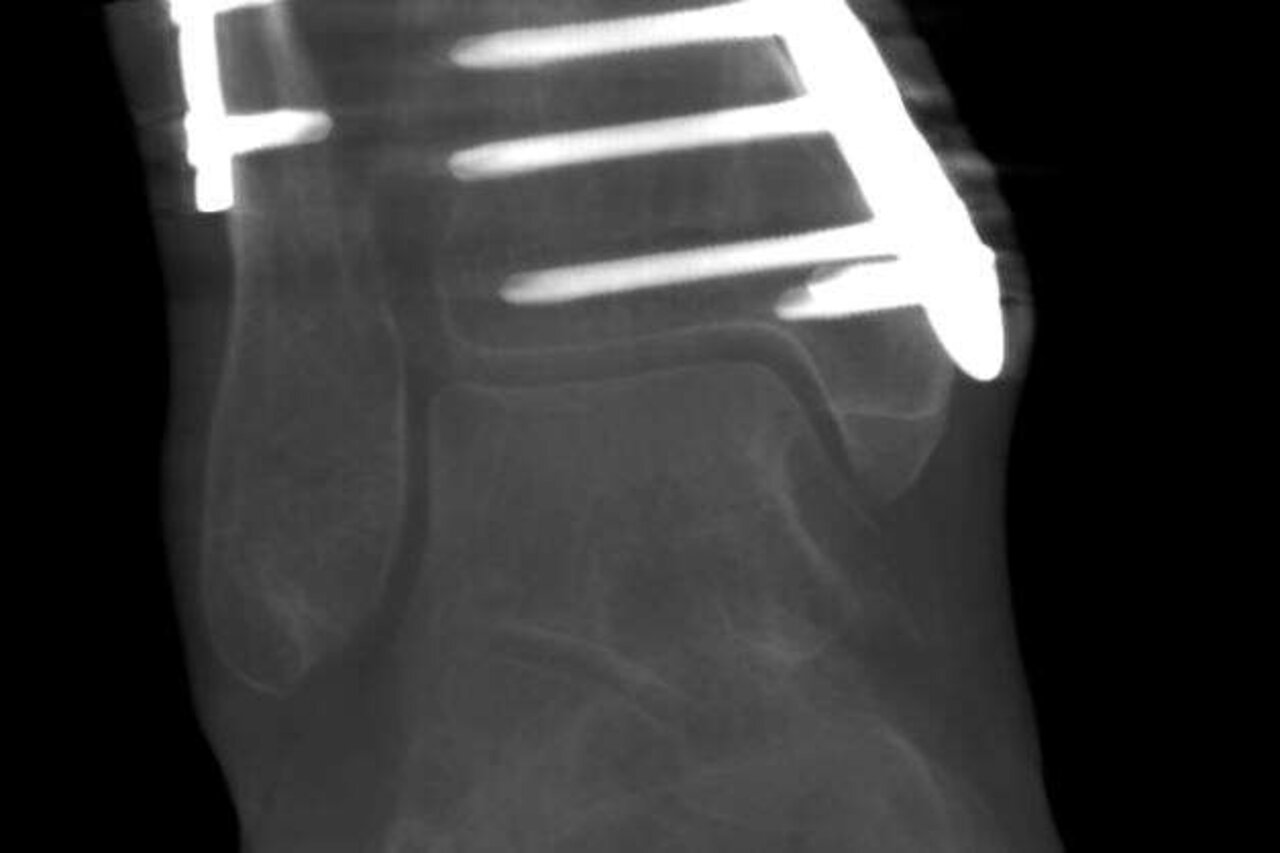

Sprunggelenkfraktur nach Operation

Sprunggelenkfraktur nach OSteosynthese AP